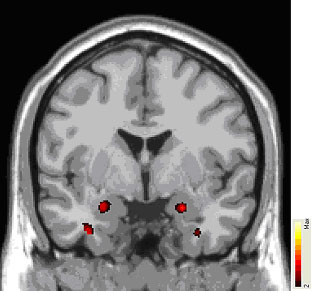

Differences in the working tissue of the brain, called grey matter, have been linked to impaired functioning of an emotion-regulating circuit in patients with borderline personality disorder (BPD). People with BPD had excess grey matter in a fear hub deep in the brain, which over-activated when they viewed scary faces. By contrast, the hub's regulator near the front of the brain was deficient in grey matter and underactive, effectively taking the brakes off a runaway fear response, suggest researchers supported in part by NIMH.

Suspecting that this functional impairment mirrors structural differences — as has been found in depression — the researchers next used anatomical MRI to compare grey matter in the same patients and healthy controls. Consistent with the fMRI results and the earlier findings, grey matter density was increased in parts of the amygdala and decreased in parts of the ACC, in BPD patients relative to controls. This suggested an abnormality in the number or architecture of neurons in these key components of the emotion-regulating circuit, which other evidence links to impaired functioning of the serotonin chemical messenger system.

Patients with borderline personality disorder had significantly higher density of grey matter, the brain's working tissue, in the brain's fear hub, the amygdala (red areas). MRI scan data shows where patients and controls differed.